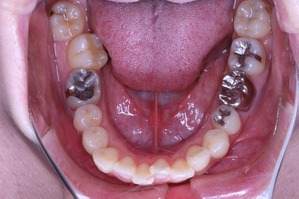

虫歯治療はきちんとされてますが、奥歯に全部銀歯の状態の歯があります。

当然、神経もない歯です。治療されたのはだいぶ前とのことでした。

しかしながら、いつ治療したか記憶にない銀歯があります。神経もとってしまってますし、中がどのような状態になっているか把握できません。治療中に歯がとれてしまい、結果的に抜歯となってしまう可能性もございます。

結論としては、治療期間が長くかかってもかまわないので、銀歯を抜いて矯正治療をしたいとのことでした。

もともとは

上の歯列はどうでしょうか?